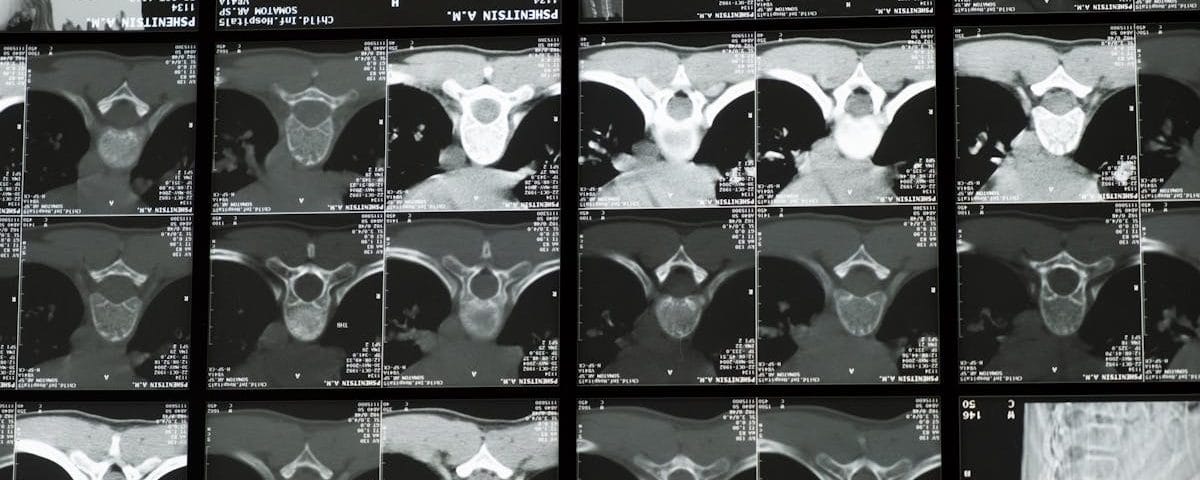

La décompression neurovertébrale est une technique qui consiste à appliquer une force de traction contrôlée sur la colonne vertébrale. Cette méthode vise à réaligner et à soulager la pression exercée sur les disques intervertébraux, permettant une meilleure circulation sanguine et un apport nutritionnel aux tissus environnants. Cela se traduit par une réduction des douleurs et une amélioration des fonctions corporelles.